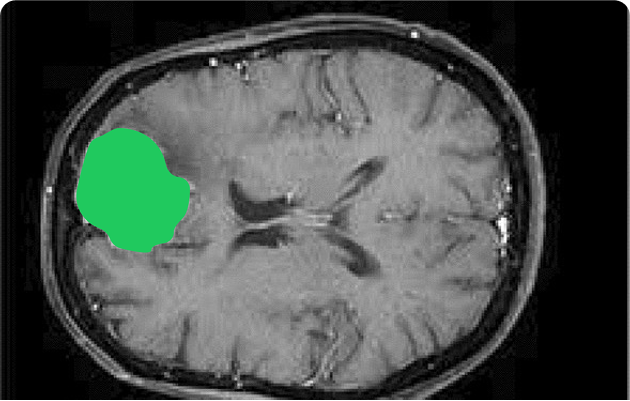

How can an annotator segment a faint, irregular tumor on multi-slice MRI with overlapping tissues and modality-specific contrast?

- Semantic segmentation: Classify each pixel to map organs and abnormalities. For radiology (organ and tumor segmentation), neurology (brain structure mapping), ophthalmology (retinal layer analysis).

- 3D annotation: Label volumetric scans from MRI or CT for higher precision. Used in neurosurgery (brain tumor planning), radiology (multi-slice CT/MRI), cardiology (vessel and chamber analysis).